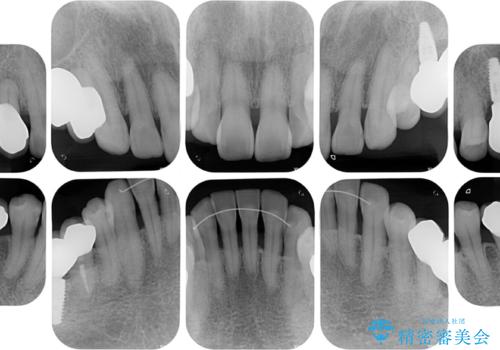

治療前は磨き残しが多く見られ、全体的に歯肉が腫れている状態でしたが、抜歯の必要な歯を抜いたことで口腔内の環境が改善され、磨き残しも少なくなってきました。

インプラントにより咬合が回復したことで、治療開始時に認められた上顎前歯の動揺も改善されました。